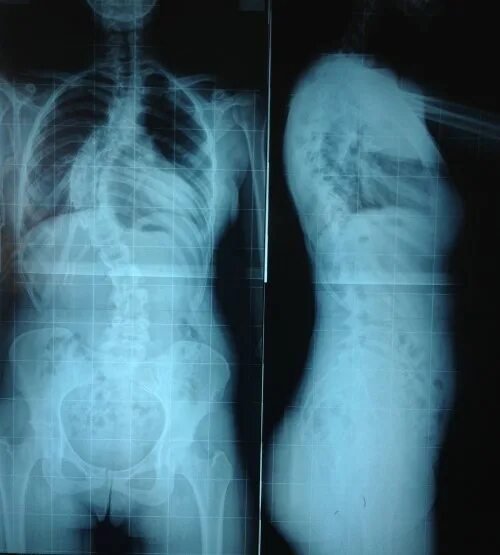

Сколиоз 4 степени инвалидность